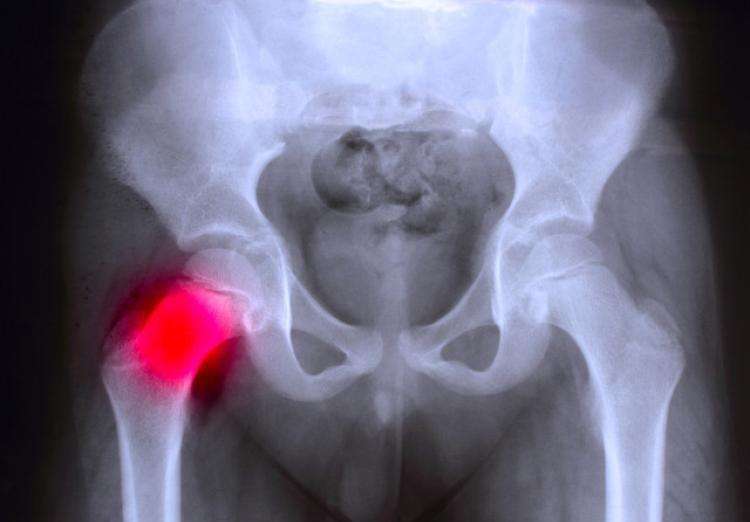

三、髋关节发育不良

髋关节发育不良也是拉布拉多比较常见的遗传病之一,后肢无力,喜欢卧着,起立困难,走路摇摆,很多时候,甚至会有“兔子跳”的走路形态。最早可能出现在5个月的时候。随着病情的恶化,最终将无法行走。

遗传、营养不良以及不充分或是过量的运动是最主要的原因,所以从小就应该要注重给拉拉做好补钙的工作哦,可购买钙片给狗狗喂食,哪款钙片比较好呢?可以参考下面的: